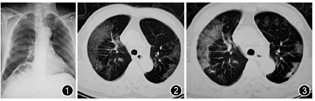

例2 女,55岁,甘肃省天水市麦积区人。因"咽痛2 d",于2020年1月31在天水市第二人民医院发热门诊就诊并收入院。患者在1月20日与武汉回天水市的亲戚一起吃饭,该亲属于2020年1月28日出现高热,明确诊断为新型冠状病毒肺炎。入院前2 d无明显诱因出现咽痛,无发热、咳嗽、咳痰、腹泻。入院查体:咽红,双侧扁桃体无红肿。双肺呼吸音粗。2020年1月31日血常规示白细胞计数为3.43×109/L,淋巴细胞计数为1.11×109/L。2020年2月5日血常规示白细胞计数2.81×109/L,淋巴细胞计数0.65×109/L。动脉血气分析(未吸氧)PaO2为80 mmHg,PaCO2为32 mmHg,氧合指数为381 mmHg。2020年2月7日血常规示白细胞计数为3.19×109/L,淋巴细胞计数为0.88×109/L,C反应蛋白为15.3 mg/L,ESR为26 mm/1 h。发病早期X线胸片提示有感染征象(图4),复查胸部CT符合病毒性肺炎的影像学表现(图5,图6)。

先后5次咽拭子病毒核酸检测均为阴性,给予高渗盐雾化诱导排痰后痰标本送新冠病毒核酸检测阳性,确诊为新型冠状病毒肺炎普通型。